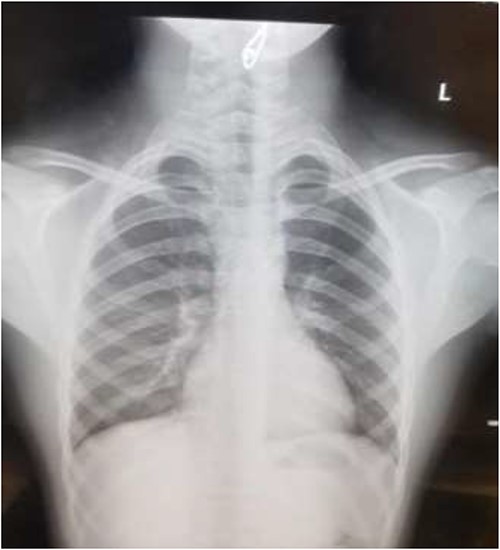

AP chest radiograph showing the sharp-edged radio-opaque object.